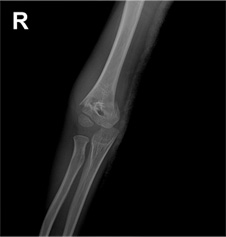

과상부 골절 수술 전

x-ray 사진